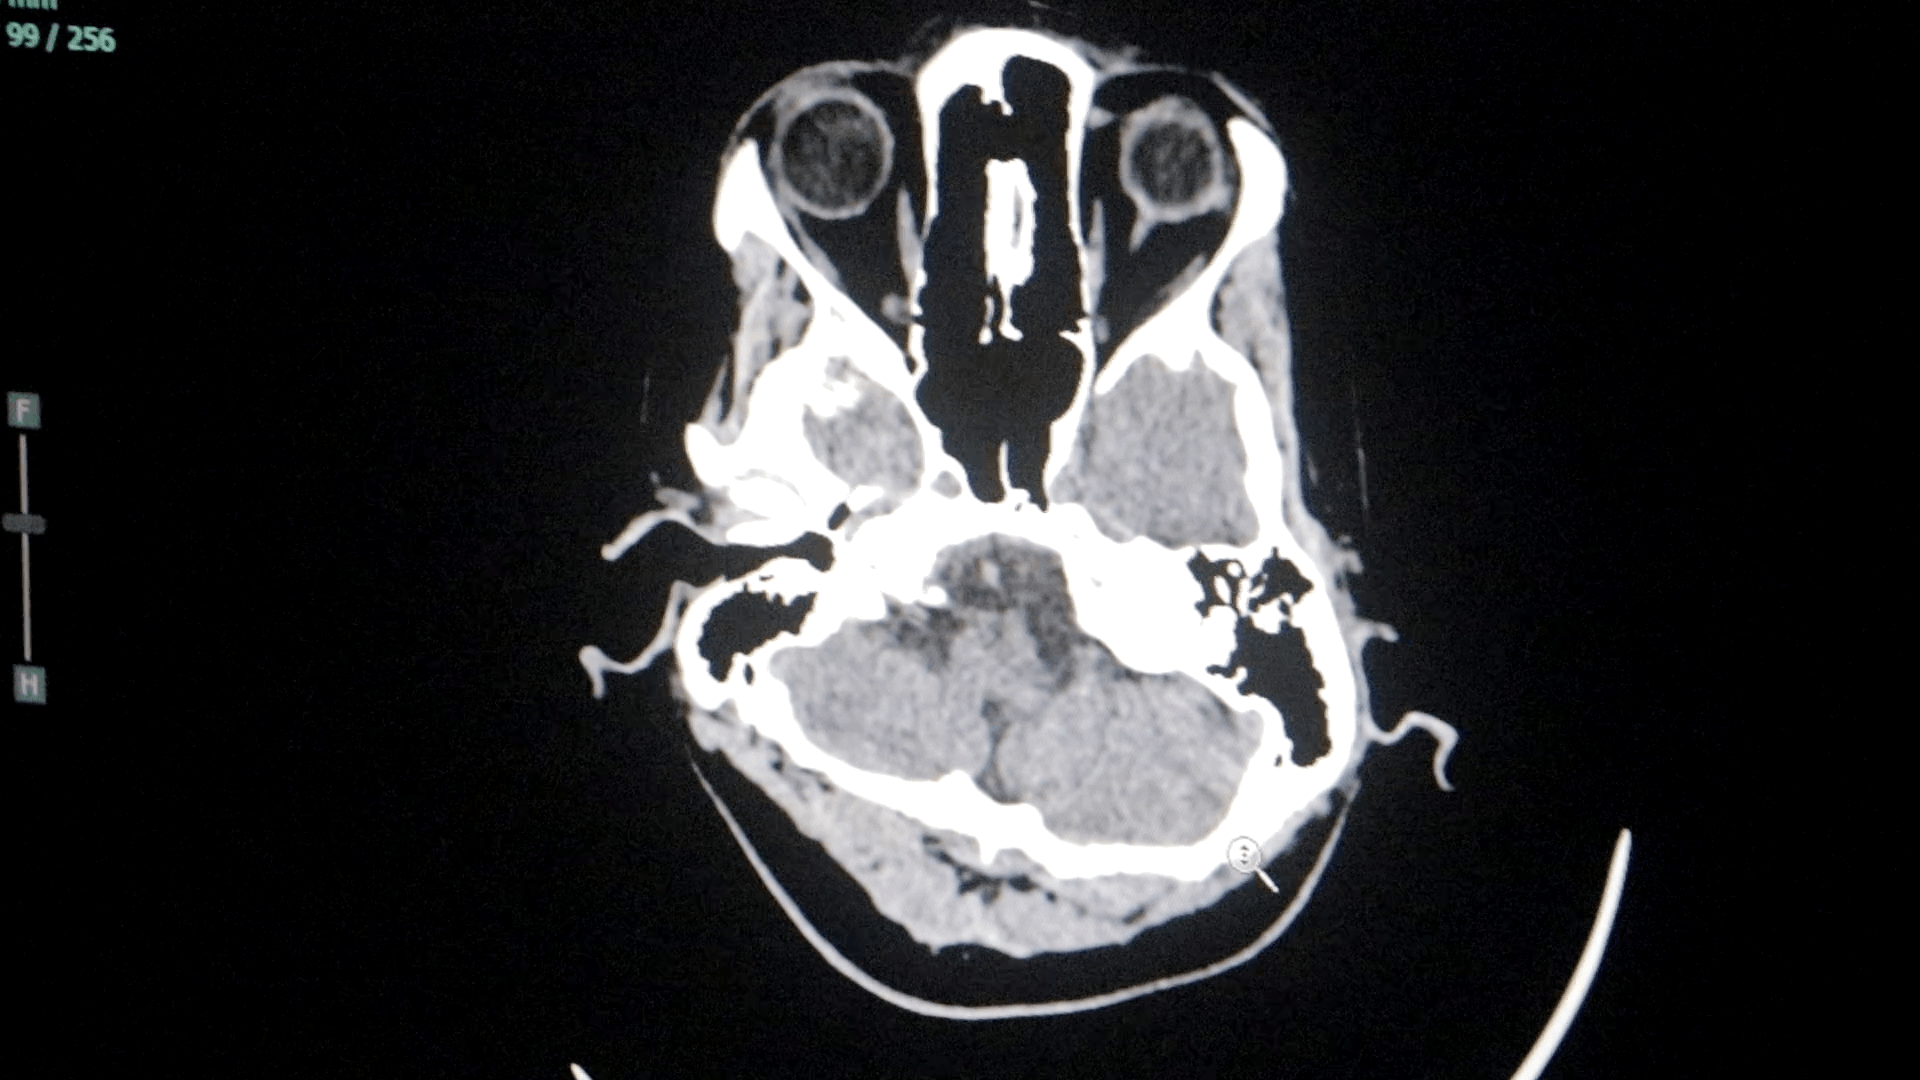

Durante el año, el servicio logró dar respuesta a un amplio abanico de patologías neurológicas de alta complejidad, incluyendo cuadros vasculares, tumorales y emergencias neuroquirúrgicas, consolidando al Parque de la Salud como centro de referencia regional.

En el área de emergentología, el servicio tuvo una fuerte intervención durante 2025, principalmente en casos de traumatismos de cráneo derivados de accidentes.